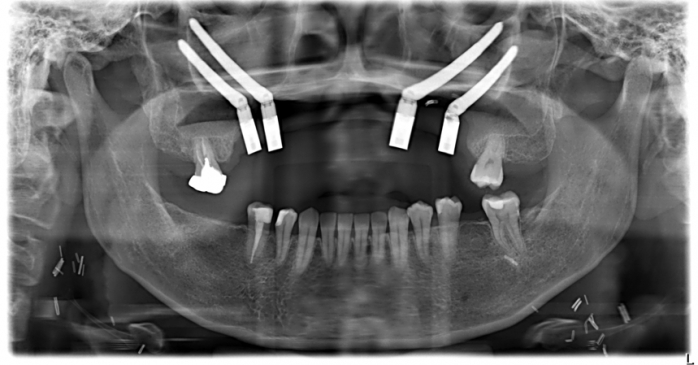

40歲的許小姐於2024年前往中山醫學大學附設醫院(以下簡稱中山附醫)口腔顎面外科就醫,確診為上顎牙齦癌,須切除大範圍上顎骨,不僅影響外觀,口內鄰近腫瘤的10顆牙齒亦需一併拔除。醫療團隊於術前運用電腦數位模擬技術,精準規劃腫瘤切除範圍、術後牙齒重建位置,並模擬將植體植入顴骨,以彌補上顎骨缺損。

手術當日,由中山附醫口腔顎面外科邱昱瑋、陳怡孜及陳珮吟三位主治醫師組成的醫療團隊主導,結合電腦數位模擬、切割導版與電腦導航系統輔助,依序完成腫瘤切除範圍確認、術後牙齒排列模擬,以及顴骨植體植入定位。最終於同一日內一次完成上顎口腔癌腫瘤切除、頸部淋巴清除、顴骨植牙及游離皮瓣重建等複雜手術,大幅縮短整體治療時程,降低患者身體負擔。術後,許小姐已成功恢復正常咀嚼功能,生活品質明顯提升。